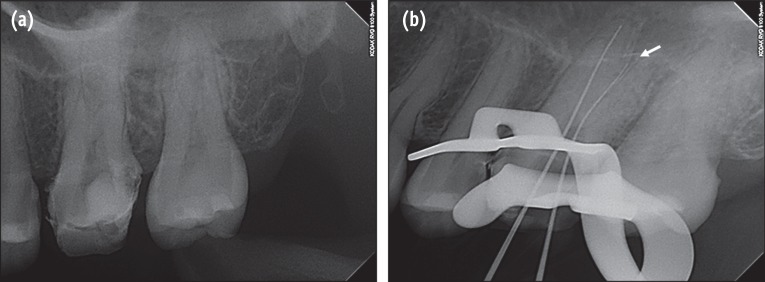

A 26-year-old woman was referred from a private dental clinic to Wonkwang University Dental Hospital for root canal treatment of maxillary left first molar. The patient's medical history was noncontributory. Medical history revealed spontaneous pain on the upper left side of her face for the past several days. Clinical examination showed a large distal temporary restoration and tenderness to percussion on the maxillary left first molar. Diagnostic radiograph showed the presence of subgingival caries in the distal area of the tooth (

Figure 1a). On the basis of clinical and radiographic examination, the patient's condition was diagnosed as pulp necrosis with acute apical periodontitis and endodontic treatment was recommended.

After profound anesthesia and rubber dam isolation, temporary restoration was removed. The pulp chamber was rinsed using 2.5% sodium hypochlorite. The evaluation of pulpal floor using an endodontic explorer revealed only 2 obvious canal orifices: mesiobuccal and palatal. Working length of the mesiobuccal and palatal canals was determined using an apex locator (Root ZX, Morita, Tokyo, Japan). The radiograph for determining the working length indicated a possibility of furcal perforation on buccal root (

Figure 1b). To rule out the occurrence of perforation and the presence of any additional roots/canals, CBCT imaging of the tooth was performed. Informed consent was obtained from the patient, and a CBCT of the tooth was performed (Alphard VEGA, Asahi Roentgen Ind. Co., Kyoto, Japan) using a tube voltage of 80 kV and tube current of 8 mA. We used the D mode of the CBCT, which has the smallest field of view (FOV) covering only 2 to 3 teeth. All protective measures were taken to protect the patient from scattered radiation. Transverse slices of the tooth were obtained at different levels to determine the mesiobuccal and distobuccal canal morphology (

Figure 1(a) Preoperative periapical radiograph of the maxillary left first molar; (b) One file was placed in the mesiobuccal area and one in the palatal canal. However, when digital image was acquired, the file seemed to be inserted between the mesiobuccal and distobuccal roots. Thus, we feared that the file closer to the distal might have resulted in a perforation (white arrow).